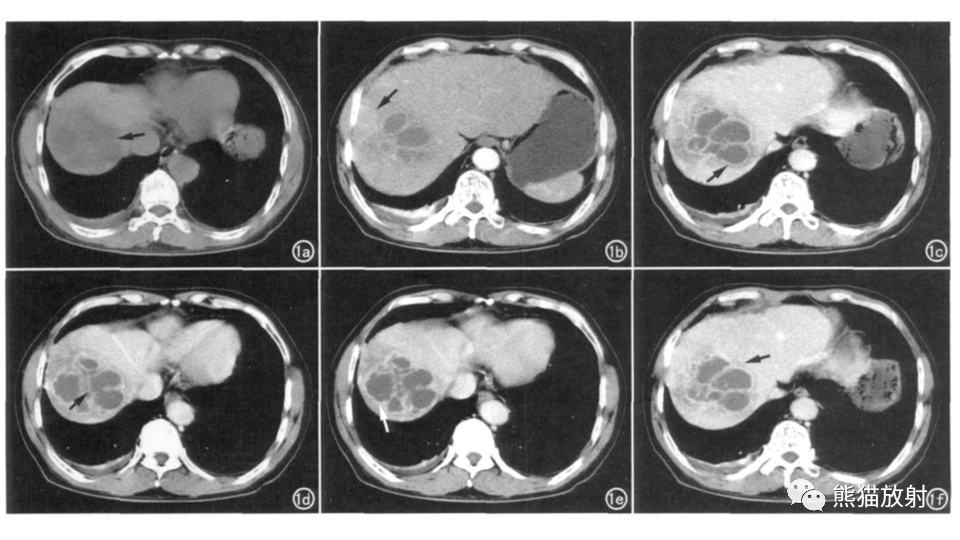

【PPT】肝内胆管细胞癌 VS 肝脓肿